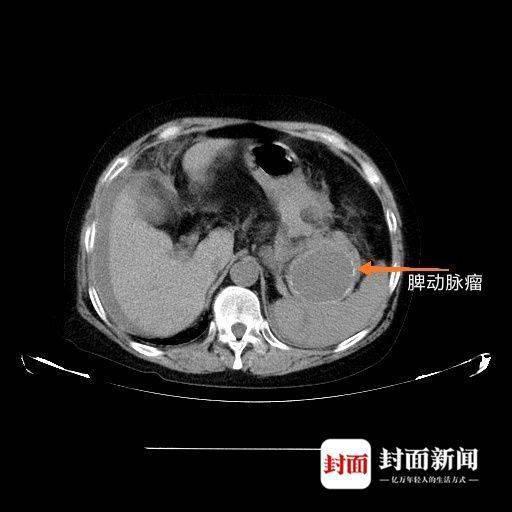

經過CT發現,張阿姨的動脈瘤位于脾門位置,大小已約6CM。而常人的脾動脈大概只有5毫米直徑,也就是說,這三年的“野蠻生長”,動脈瘤讓動脈膨脹了十倍之多,隨時都會破裂。

而在動脈瘤自發破裂后,腹腔內出血約3000ml,張阿姨當時感覺到肚子里有水在翻滾,其實就是血如同爆管的自來水不停地往外涌。“脾動脈瘤是內臟動脈瘤的一種,也是最常見的一種,內臟動脈瘤破裂出血,即使及時手術,成功搶救過來的機會也不大。”張華茂介紹,抱著不論動脈瘤破裂是多么兇險也絕不放棄的信念,他清楚的知道當務之急是控制出血,靠著自己的臨床經驗先游離了脾動脈,快速而準確地結扎了脾動脈,再切除脾臟和脾動脈瘤,希望手術還能為她創造一線生機。